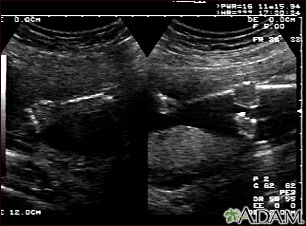

Your health care provider can diagnose this condition with a pregnancy ultrasound.